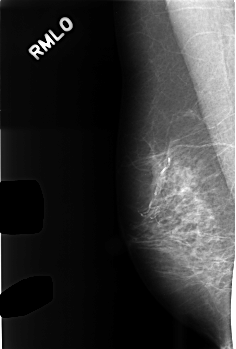

Digital Database for Screening Mammography

Volume: benign_14 Case: C-0476-1

C_0476_1.RIGHT_MLO

RIGHT_MLO LINES 4536 PIXELS_PER_LINE 3064 BITS_PER_PIXEL 12 RESOLUTION 50 NON_OVERLAY